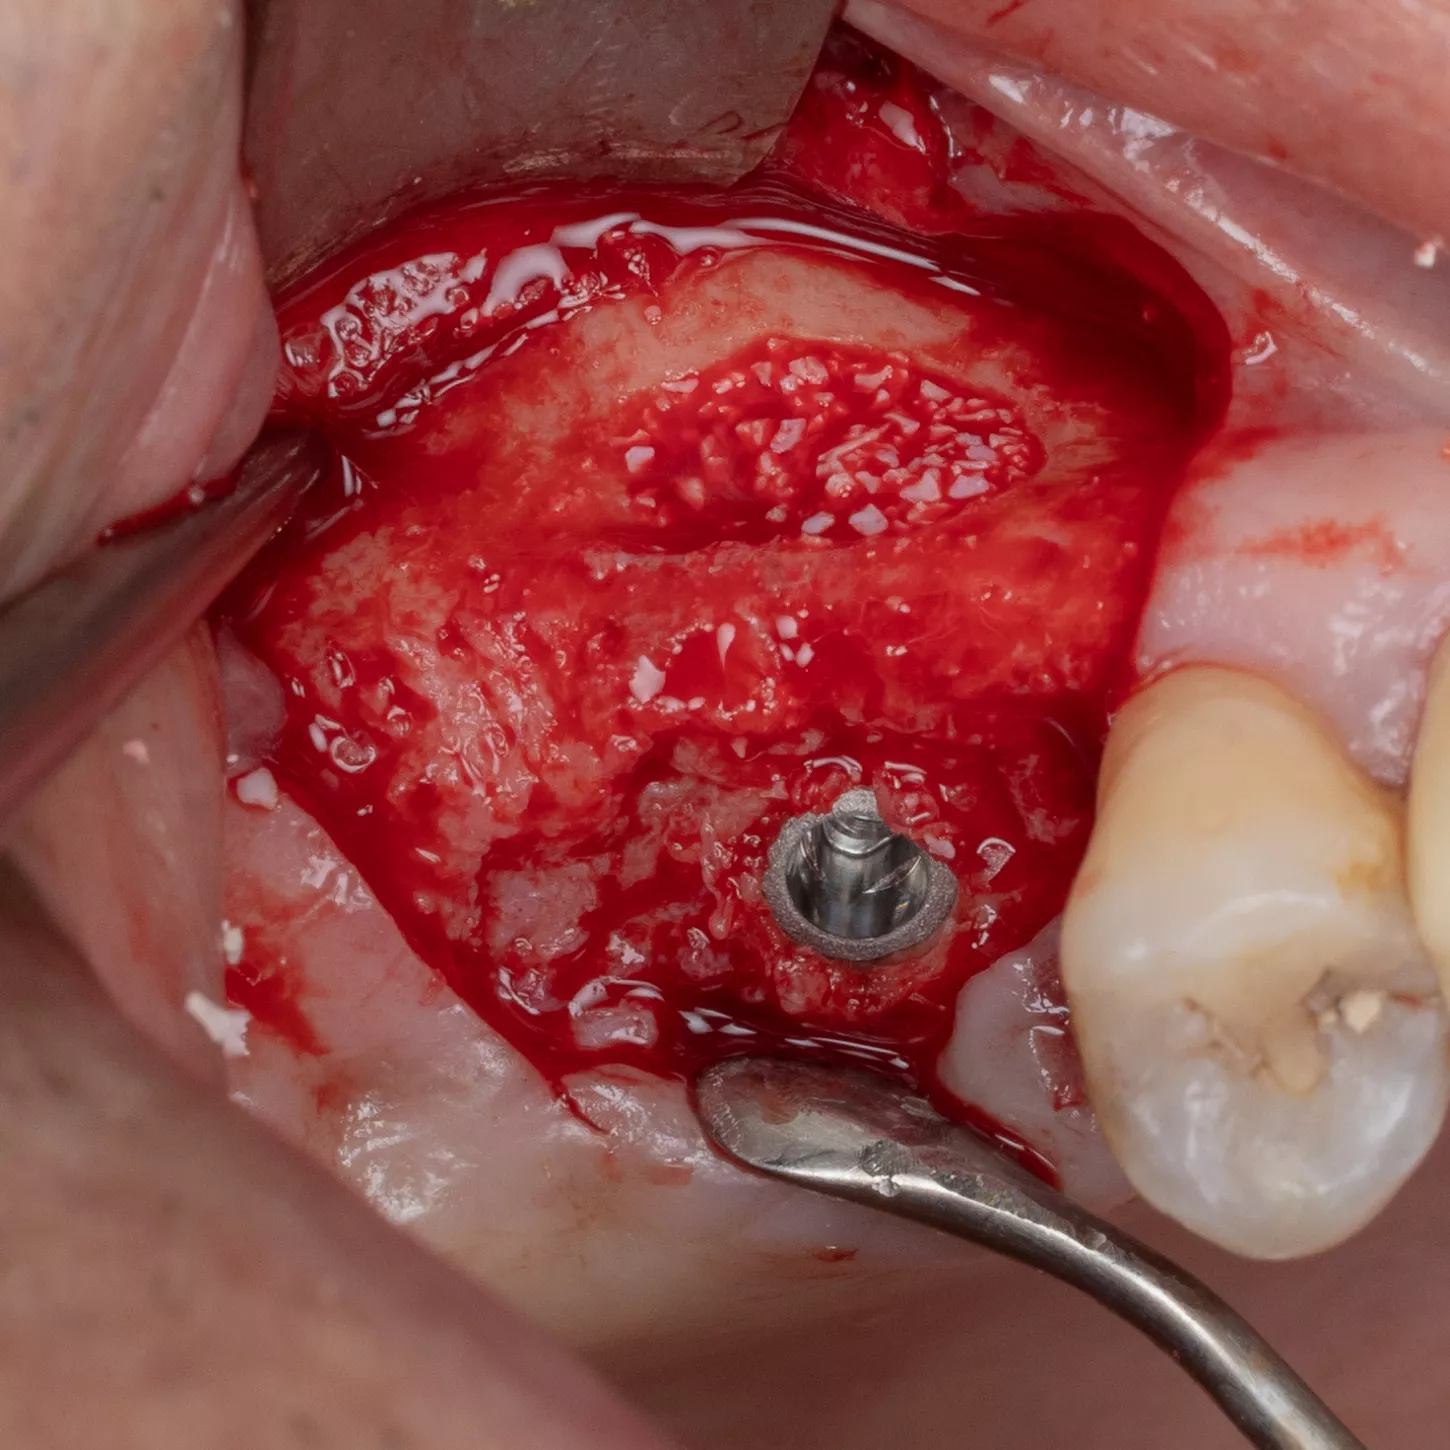

16. Prior to implant placement, filling of the palatal and mesial area of the sinus cavity with axenogenic biomaterial (XenoGraft, Straumann®).

17. Filling and compression using a graft packer in the mesio-palatal direction.

18. The sinus cavity is densely packed with the bone graft composite to support the implant.

19. The Anthogyr Axiom® BL X3 Ø 4.0 mm, length 10 mm implant is inserted.

20. Verification of correct positioning of the implant at a depth 1 mm below the crest of the bone.

21. Placement of the cover screw tightened by hand using a screw wrench.